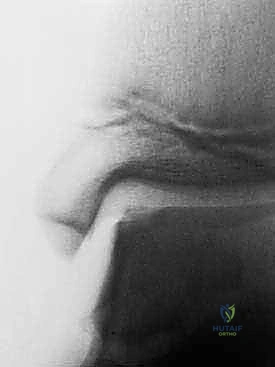

- الأشعة السينية (X-rays): لاستبعاد الكسور العظمية وتقييم الهيكل العام للمفصل. في بعض الأحيان قد تظهر الآفات العظمية الكبيرة، لكن الأشعة السينية لا تظهر الغضروف.

- التصوير بالرنين المغناطيسي (MRI): هو المعيار الذهبي لتشخيص آفات الغضروف العظمي. يتيح الرنين المغناطيسي عالي الدقة للدكتور هطيف رؤية الغضروف بوضوح، تحديد حجم الآفة، عمقها، وموقعها بدقة متناهية، بالإضافة إلى تقييم العظم الكامن تحتها.